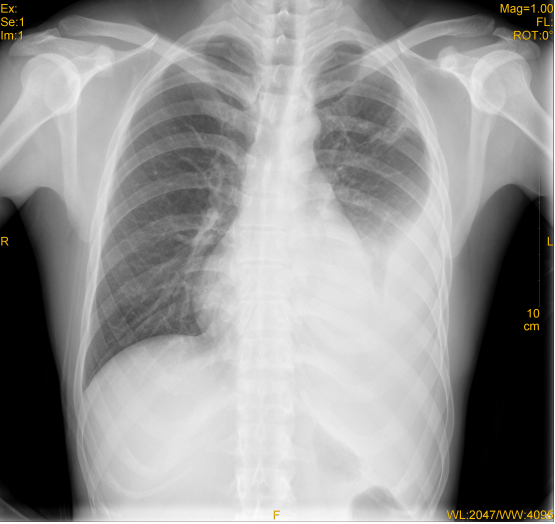

患者完善血常规、凝血功能、胸片检查,结果如下: 血常规:白细胞 7.5×109/L,N 55%,L 34%,红细胞 3.65×1012/L,血红蛋白122g/L。 血沉:100mm/h 凝血功能:凝血酶时间(TT):16.6s 凝血酶原时间(PT):10.9s 活化部分凝血酶时间(APTT):26.3s 胸片: